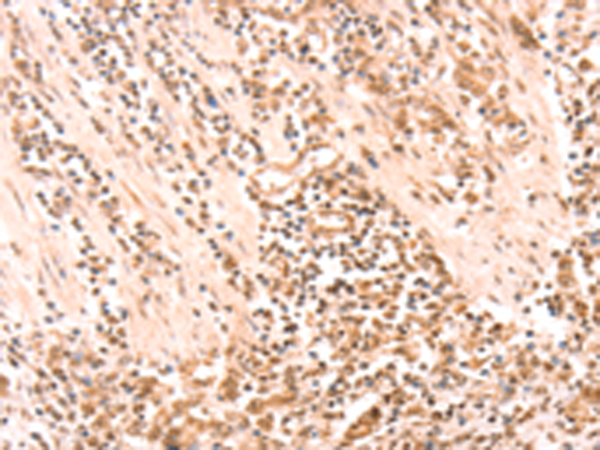

分类: 科研抗体货号: P11181别名: AMD; SAMDC; ADOMETDC应用: IHC反应种属: Human, Mouse, Rat